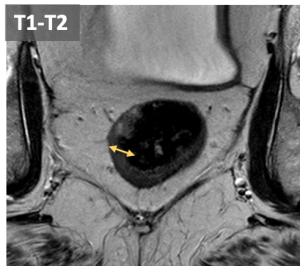

Differences in T2w signal intensity of the rectal wall layers allow accurate assessment of mural invasion and regional spread. The mucosa and muscularis propia appears hypointense while the submucosa is hyperintense.

- T1-T2: Preservation of the hypointense muscularis propia indicates tumor confined to the wall. Differentiation of T1 or T2 is not possible without submucosal edema.